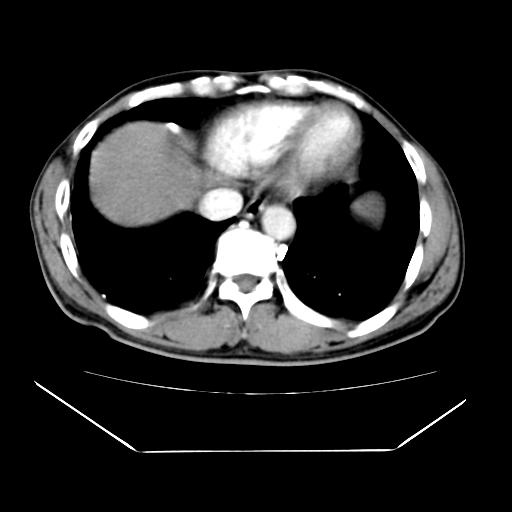

男性,55岁,外院体检afp明显升高,但b超未发现异常,否认乙肝病史。来我院ct增强。有延时扫描。

延时扫描完全充填,血管瘤

肝脏右叶动脉期可见低密度影,至延迟期被充填,考虑血管瘤可能性大。

不排除肝右叶肝癌可能。

如果这个是癌灶的话则下腔静脉有瘤栓可能

肝6段血管瘤

血管瘤可能性大。

考虑肝右静脉影。